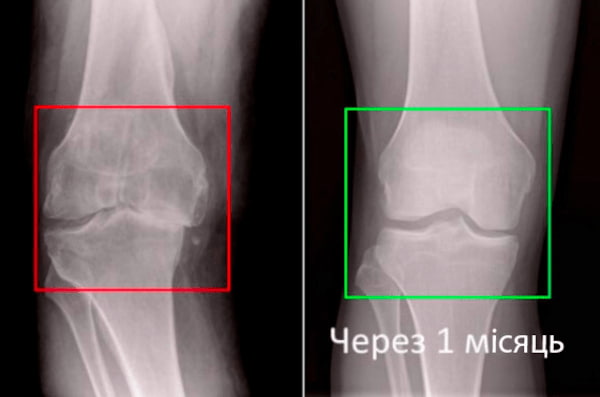

Візьміть до уваги знімок колінного суглоба 63-річного пацієнта за 1 місяць користування Artrolife - суглоб повністю регенерувався.